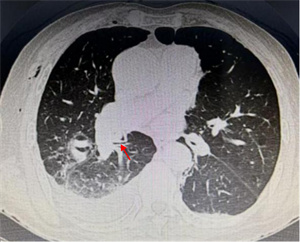

鲜美的动物骨髓深受很多人喜爱。一位中年患者清晨急匆匆来到我院呼吸科住院部。主诉前一天晚餐吸食猪骨髓时,不慎将食物吸入气管,出现反复剧烈咳嗽,并有咯血。我院呼吸科医生在其急诊胸部CT中发现右中间段支气管有一 “刀片样异物” 横在管腔内。评估病情并做好预案后,医生顺利取出一锐利骨片异物,有效阻止了 “利器” 造成肺内出血恶果的发生。